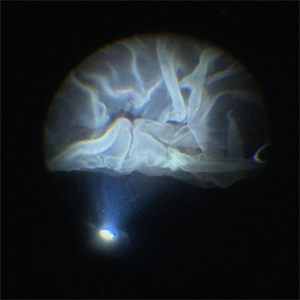

Intraoperative View of a Giant Retinal Tear

Intraoperative view of 12 year old child with Giant retinal tear with Retinal detachment.

Imaging device: Lumera Proveo 8

Condition/keywords: GIANT RETINAL TEAR, PVR, Retinal Detachment